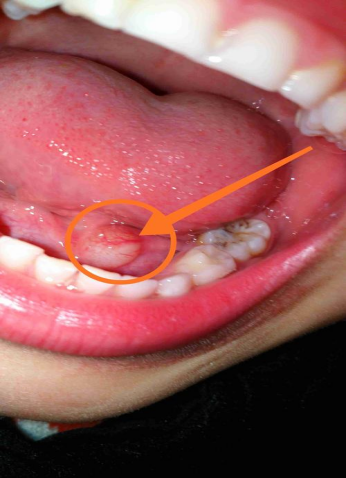

二、它长什么样?——主要症状和表现

舌下腺囊肿通常有两种类型:

1. 单纯型(最常见):

(1)位置:位于舌头下方的一侧。

(2)外观:呈淡蓝色或淡粉色,半透明,像一个充满水的气球。

(3)触感:质地柔软,无痛或有胀痛感。